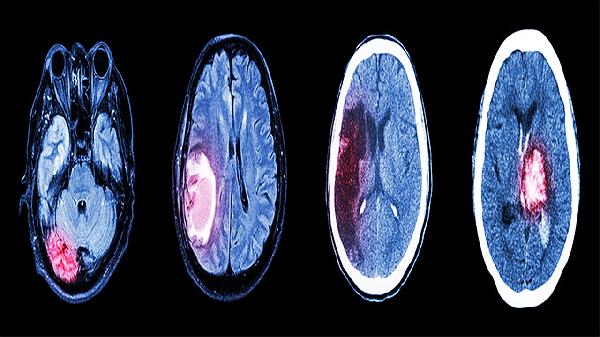

头脑血管堵塞是危及生命的严重疾病,可能导致中风、脑缺血或脑梗塞等情况,需立即就医接受治疗。其危害取决于血管堵塞的程度以及对脑组织的影响。 血管堵塞的原因包括血脂异常、动脉硬化、血栓形成、高血压、糖尿

脑梗死患者护理全攻略:饮食调理与药物管理助力康复

脑梗死是一个需要细心护理的疾病,患者在日常生活中需要遵医嘱按时服药,关注饮食和生活起居的调理,并定期到医院进行复查以了解病情变化。这样的护理不仅有助于康复,还能有效预防复发。 1、药物治疗:患者应在